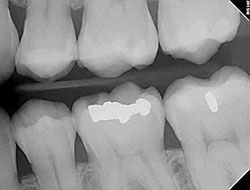

x-rayUsing the most advanced dental technology possible is just as important as staying up-to-date on the latest treatment techniques. Because our practice is dedicated to providing your child with the safest and most convenient treatment options available, we utilize advanced digital X-ray technology in our office.

Because we care about your child's entire body's health and well-being, we believe that reducing the amount of radiation exposure is extremely important. Although the amount of radiation used in dental X-rays is very small, the effect is cumulative, so all radiation counts. Digital X-rays can reduce your child's exposure to radiation by up to 80%!

• The digital images can be enlarged and manipulated, giving the doctor a clear, more detailed look at your child's teeth.